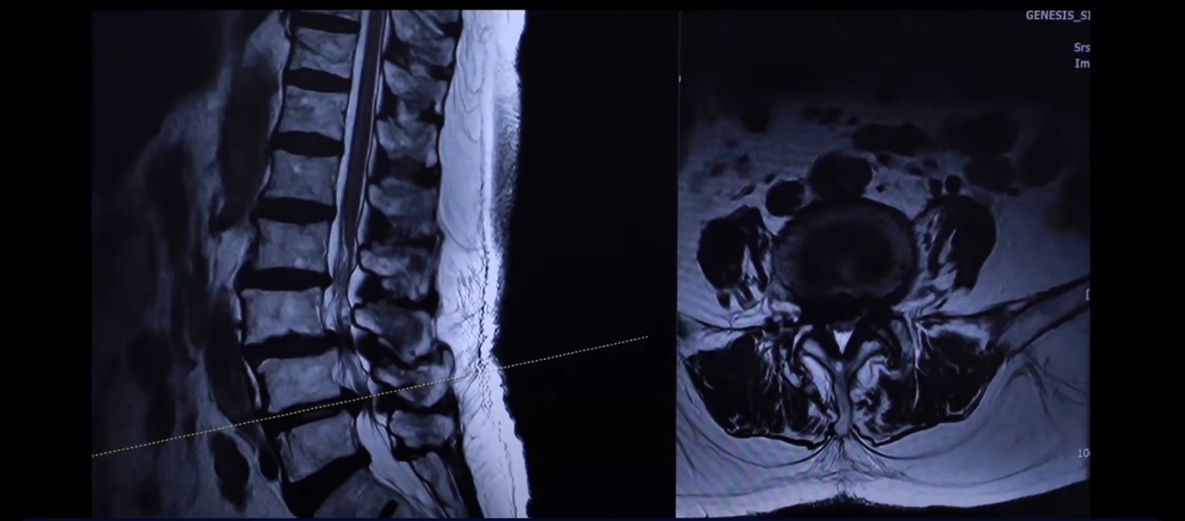

이분 76세 여자 환자분 MRI를 보겠습니다. 이분 MRI를 보시면 보시다시피 허리 여러 마디가 퇴행돼 있고 전방전위가 있습니다. 뼈가 밀려나가 있죠.

그리고 이렇게 뼈가 밀려나간 전방전위증을 가지신 분들은 허리가 오랫동안 아프신 분들이 많습니다. 이분도 한 5년 정도 허리가 아프셨고 그때그때 신경 주사 맞으면서 버티고 사셨는데 신경주사라는 건 맞다 보면 점점 효과가 떨어집니다. 그리고 결국은 다리 증상들이 심하게 생겨서 걷지를 못하게 되시는 거죠. 걷는 거리도 점점 짧아지고 다리는 왜 저리게 되냐면 이분의 이렇게 전방전위증이 있는 마디를 보면 척추관이 좀 좁아져 있지만 아주 많이 좁지 않습니다.

어떻게 척추관 협착증이 수술 없이 치료가 될 수 있는지 많은 분들이 이렇게 신경이 눌려 있으면 어떻게든 이 주변을 수술로 파내서 신경 구멍을 넓혀줘야만 한다고 생각을 하는데, 전방전위증, 척추관 협착증이 증상이 생기고 악화되는 이유는 신경 구멍만이 좁아져서 그런 게 아니라 아니라 동시에 이분이 나이가 들면서 76세시죠. 그러면 근육이 동시에 나빠지는 겁니다. 어떻게 나빠지냐 이미 40대부터 근육이 빠른 속도로 줄기 시작해서 76세면 젊었을 때 근육의 50%~60%밖에 남지 않습니다.

그래서 이렇게 근육 상태가 어떤지 이렇게 객관적으로 볼 수 있는 부분도 MRI에서 보실 수 있습니다. 그만큼 근육이 안 좋아지니까 나이가 드시면서 또 이런 근육들이 뭉쳐 있고 굳어 있고 또 기능을 잘 못하게 되니까 또 근육 자체도 뭉쳐 있으면 아픕니다. 그러니까 허리를 잘 지탱하지 못하니까 이런 신경 구멍이 좁아진 곳에서 신경이 눌리는 겁니다. 허리를 잘 지탱할 수 있도록 근육 기능들을 살려주니까 훨씬 더 신경 눌림이 덜해지고 힘을 잘 쓸 수 있고 더 잘 걷게 되는 겁니다.